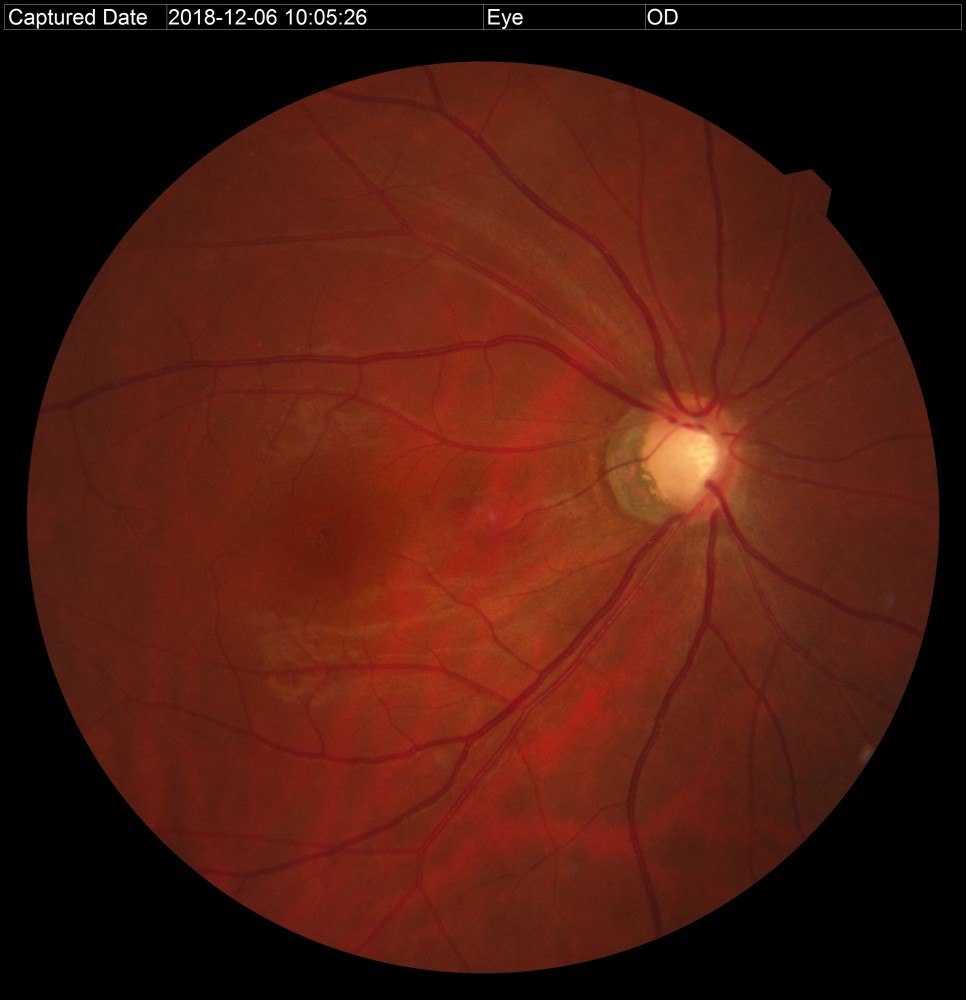

안저검사와 안구광학 단층촬영이 가능한 RS330과 OPTOS

안저 검사는 동공을 크게 하지 않고도 눈 속을 들여다 볼 수 있는 장비입니다.본원에는 안저의 중심부(30도)를 볼 수 있는 RS330과 중심+주변부(200도)까지 확인 가능한 OPTOS가 있습니다.

안저검사를 통하여 시신경의 형태, 시신경유두의 함몰비, 시신경 손상 여부 등을 확인할 수 있습니다.

녹내장 환자의 안저사진 안저검사를 통하여 녹내장 유무가 확인되면 안구광학단층촬영(OCT)을 통하여 시신경의 손상 정도를 보다 정확하게 확인합니다.